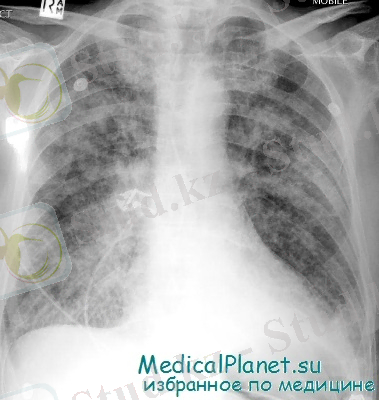

Диагностикасы. Тынысалудың дистресс-синдромын диагностикалауда рентгенологиялық әдіс қолданылады. Рентгенологиялық белгілері патологиялық процесстің дамуына байланысты. Оларды Е. К. Колесников бойынша төртке бөліп қарастырады.

Рентгенографияда - өкпенің екі жағы да диффузды инфильтрат байқалады.